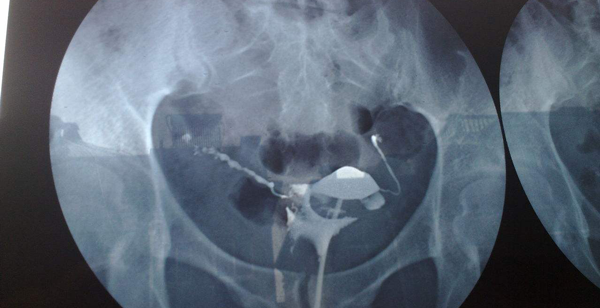

这里在来了解一下输卵管造影,输卵管造影全称为输卵管碘油造影,通常输卵管造影会根据输卵管的阻塞程度来判断疼痛的,因为在术中引起子宫腔和宫颈管扩张,所以导致疼痛,做过的女性应该知道这是有多痛。

那么这里试管取卵痛还是造影痛呢,其实据很多患者反映取卵的疼痛要比输卵管造影好得多,所以对于试管取卵和造影那个痛的争论来说,其实真的是没有输卵管造影痛,但是腹部取卵危害却是要注意的。